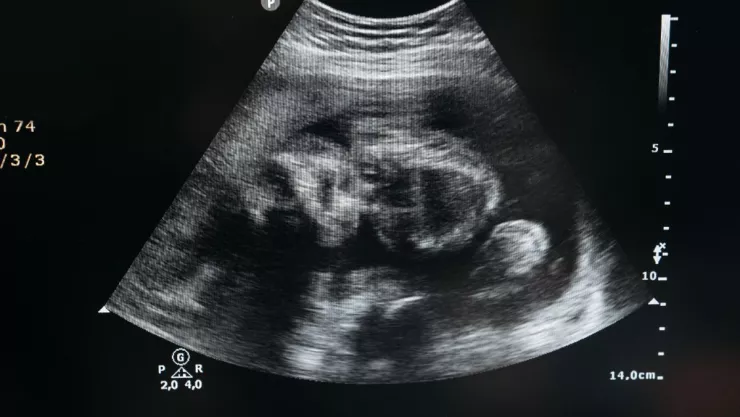

Debido a la emergencia, los doctores advirtieron a los padres de la bebé que tenían que operar. El grupo de especialistas detectó que había un total de ocho fetos dentro de un quiste.

Cada feto medía entre 3 y 5 centímetros de largo, reportó el Doctor Dr. Mohammed Imran a cargo de la cirugía.

"En el diagnóstico inicial, se encontró un quiste o sustancia tumoral. Estaba situado debajo del diafragma. Decidimos extraerlo mediante una operación, que se realizó el 1 de noviembre. Entonces, descubrimos ocho fetos uno tras otro dentro de la pieza”, informó el médico encargado a la prensa local.